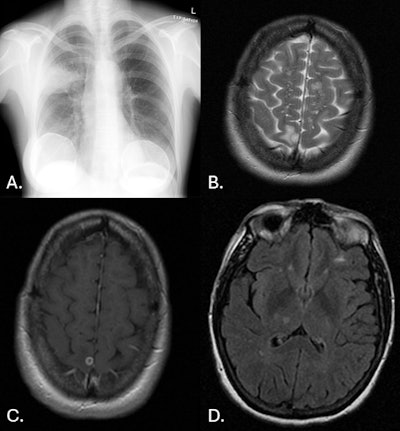

58-year-old woman. (A) CXR frontal: right upper lobe focus of consolidation. (B) MR Brain axial T2: round lesion of right parietal lobe that is hyperintense. Left frontal lobe lesion that is also hyperintense. (C) MR Brain axial T1 + contrast: right parietal lobe lesion demonstrating peripheral enhancement. (D) MR Brain axial FLAIR: round lesion of the right thalamus, which is hypointense.All images courtesy of Dr. India Plath et al and Department of Medical Imaging, Royal Brisbane and Women’s Hospital, Brisbane; presented at RANZCR 2025 ASM.